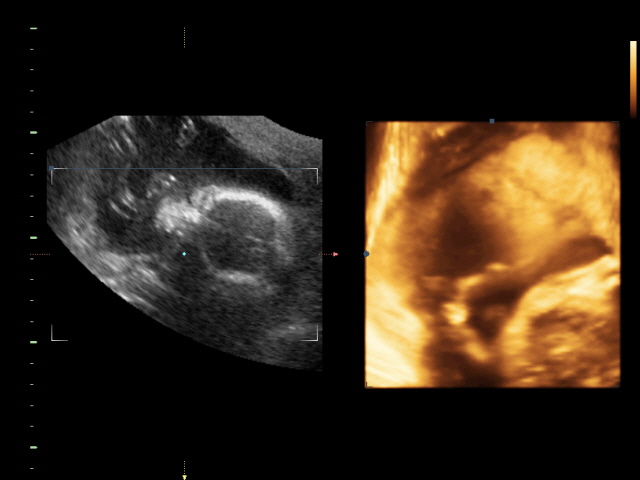

УЗИ, КТГ, доплерУраа!!!Сходили наконец-то на узи!!!!Все у нас супер!Все хорошо!!Мы перевернулись,теперь в головном предлежании.Плацента поднялась.По узи срок 22-23 недели,как и должно быть в принципе))Так же нам подтвердили мальчика,наделали видео три штуки,штук 10 фото на диске.Вообщем девочки я очень довольна.Единственное только думаю рано в 23 недели идти на 3D узи.Потому что малыш еще не до конца развился,ну зато такая память!!!Вообщем всем довольна!!!

Даже не знаю как еще отобразить свои эмоции!!!Малыш на узи сначала вел себя спокойно ручки к лицу прикладывал,будто задумался,потом стал головку прятать,не нравится нам показываться теперь((Ох как я жду этого пупса!!!!

Меня так удивило как он там лежит...ручки прикладывает к лицу.Руками дубасит меня оказывается,я думала у него ноги такие сильные,оказывается ручки.Так на папку похож..ИИИИй..милашка моя!!